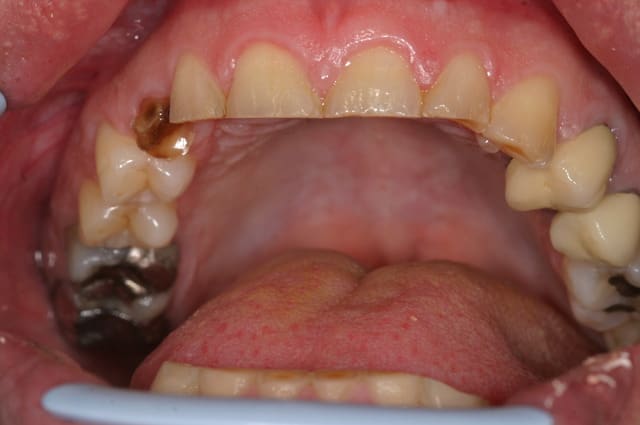

ce patient, 40 ans, non fumeur, sans de pb de santé particulier consulte pour un problème esthétique sur la 53. il est aussi inquiété par l'usure de ses incisives.

l'abrasion des incisives, l'éggression des groupes incisivo-canin maxillaire et mandibulaire pour compenser cette abrasion, et l'occlusion me laissent dubitatif.

J'avais envisagé dans un premier temps de proposer de l'ortho pour lever la supracclusion et permettre la pose d'un implant pour remplacer la 13, et reconstituer les incisives, mais l'absence d'une veritable perte de DV me laisse un peu sec pour le plan de traitement. Toutes les idées sont les bienvenues.